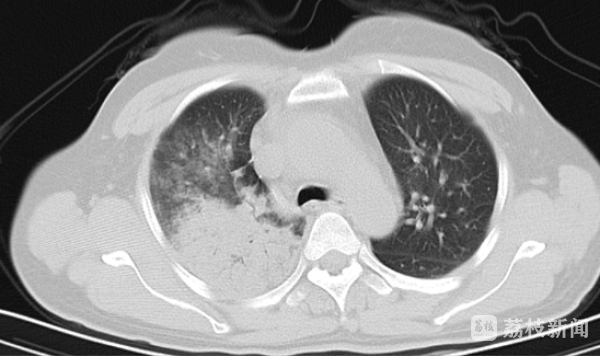

孙女士身体一直很好,突然出现出现畏寒寒战,当时未测体温,伴四肢乏力,走路不稳,测体温为39.9℃,乏力症状较前加重,且有言语混乱。家属将她送到当地医院进行治疗,效果不佳,仍有高热、言语错乱,家属焦急万分,将她送到南京市第一医院呼吸内科进行治疗。入院后,医生予布洛芬退热、抗感染治疗后,孙女士体温可下降,但数小时后体温再次上升。孙女士被转入呼吸内科重症病房进行治疗。入室时,患者表情淡漠,呼吸频快,血气分析示I型呼吸衰竭,氧合指数仅200mmHg。胸部CT可见右肺多肺叶浸润,诊断为重症肺炎。